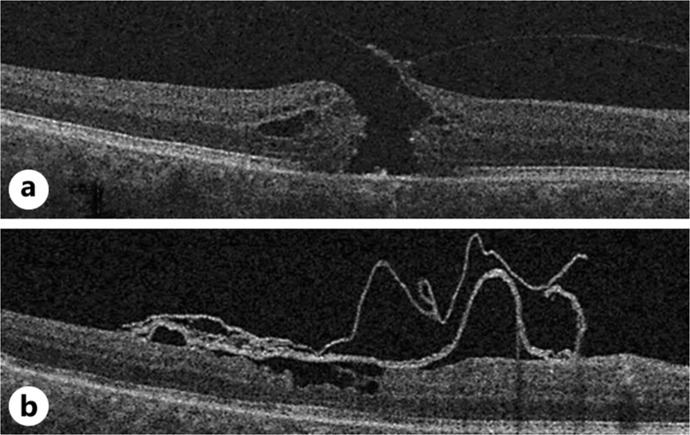

Optical Coherence Tomography of a Folded Amniotic Membrane over a Macular Hole.

Case presentation: Best corrected visual acuity improved from 35 letters after MH recurrence to 55 letters after second surgery. Despite the folding and the large size of the AM, optical coherence tomography confirmed the closure of the MH without significant symptom.